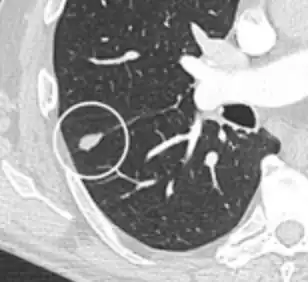

- Location: Upper lobe location is a risk factor for cancer, while a location close to a fissure or the pleura indicates a benign lymph node,[8] especially if having a triangular shape.[9]

- Margin morphology: a spiculated margin is a risk factor for cancer.[8] Benign causes tend to have a well defined border, whereas lobulated lesions or those with an irregular margin extending into the neighbouring tissue tend to be malignant.[10] In particular, spiculations are highly predictive of malignancy with a positive predictive value up to 90%.[9] Also, a "notch sign", which is an abrupt indentation of the nodule, increases the risk of cancer, but may also be found in granulomatous diseases.[9]

-

subpleural nodule.[9] -

Round well-delineated solid lung nodule with smooth border.[9] -

Lobulated nodule.[9] -

Spiculated lung nodule.[9] -

A "notch sign".[9] -

A triangular perifissural node can be diagnosed as a benign lymph node.[9]